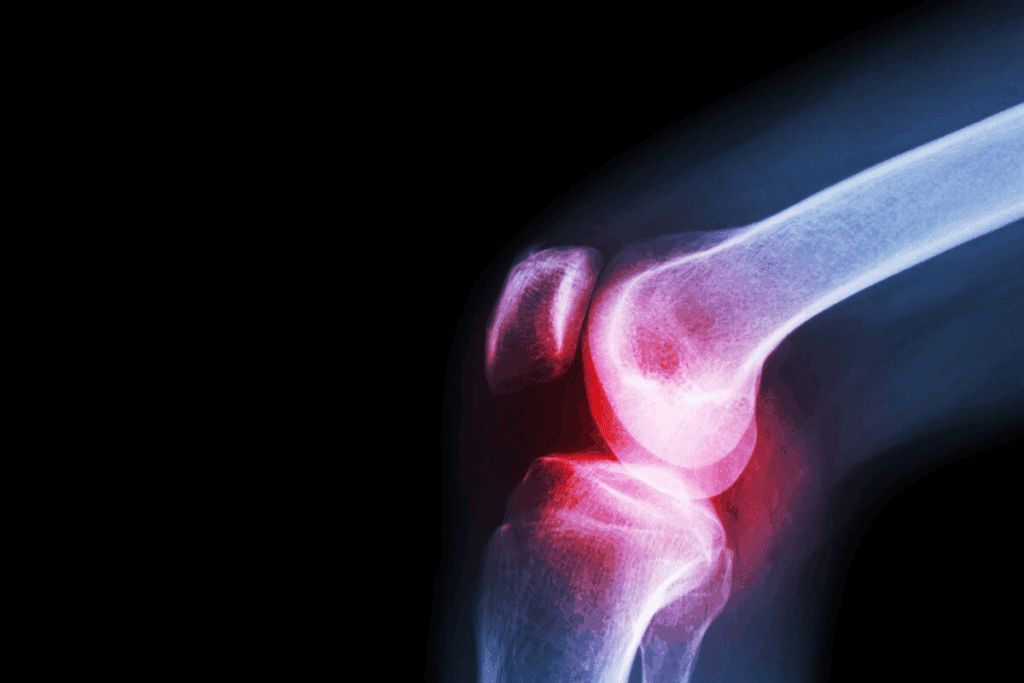

Imaging Tests (X-rays, MRI, CT Scans)

Imaging tests are key to confirming knee subluxation. We use X-rays, MRI, or CT scans to see inside the knee. These tests help us find any ligament tears, fractures, or other injuries.

| Imaging Test | Purpose | Benefits |

| X-rays | Check bone alignment and find fractures | Quick and easy to get |

| MRI | Look at soft tissue injuries, like ligament tears | Great for finding soft tissue damage |

| CT Scans | Give detailed images of bones and soft tissues | Good for complex cases |